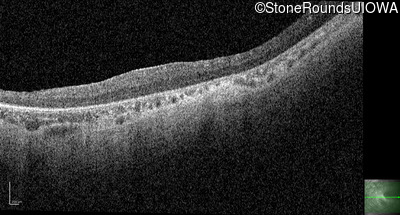

Optical Coherence Tomography - Left - 20/500 sc

Exemplar / OCT Stack

OCT Stack